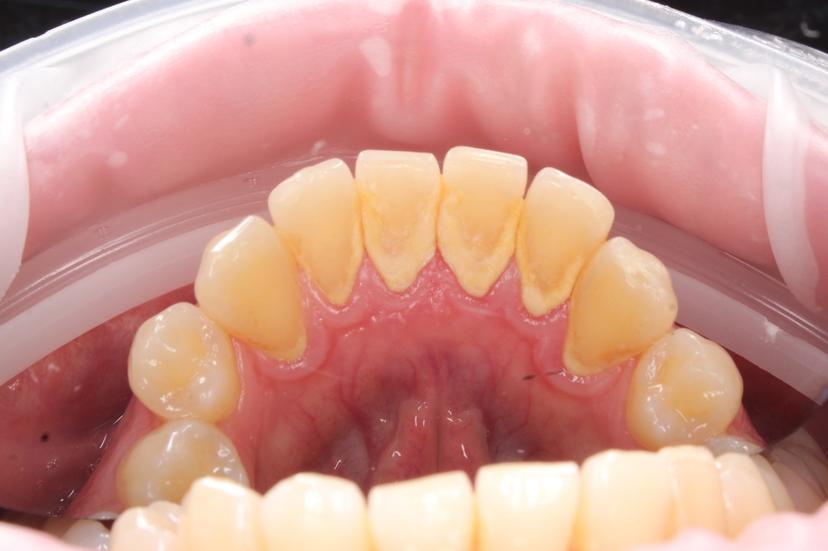

Снятие пигментированного зубного налета системой AirFlow зубов верхней челюсти

Снятие пигментированного зубного налета системой AirFlow на нижней челюсти